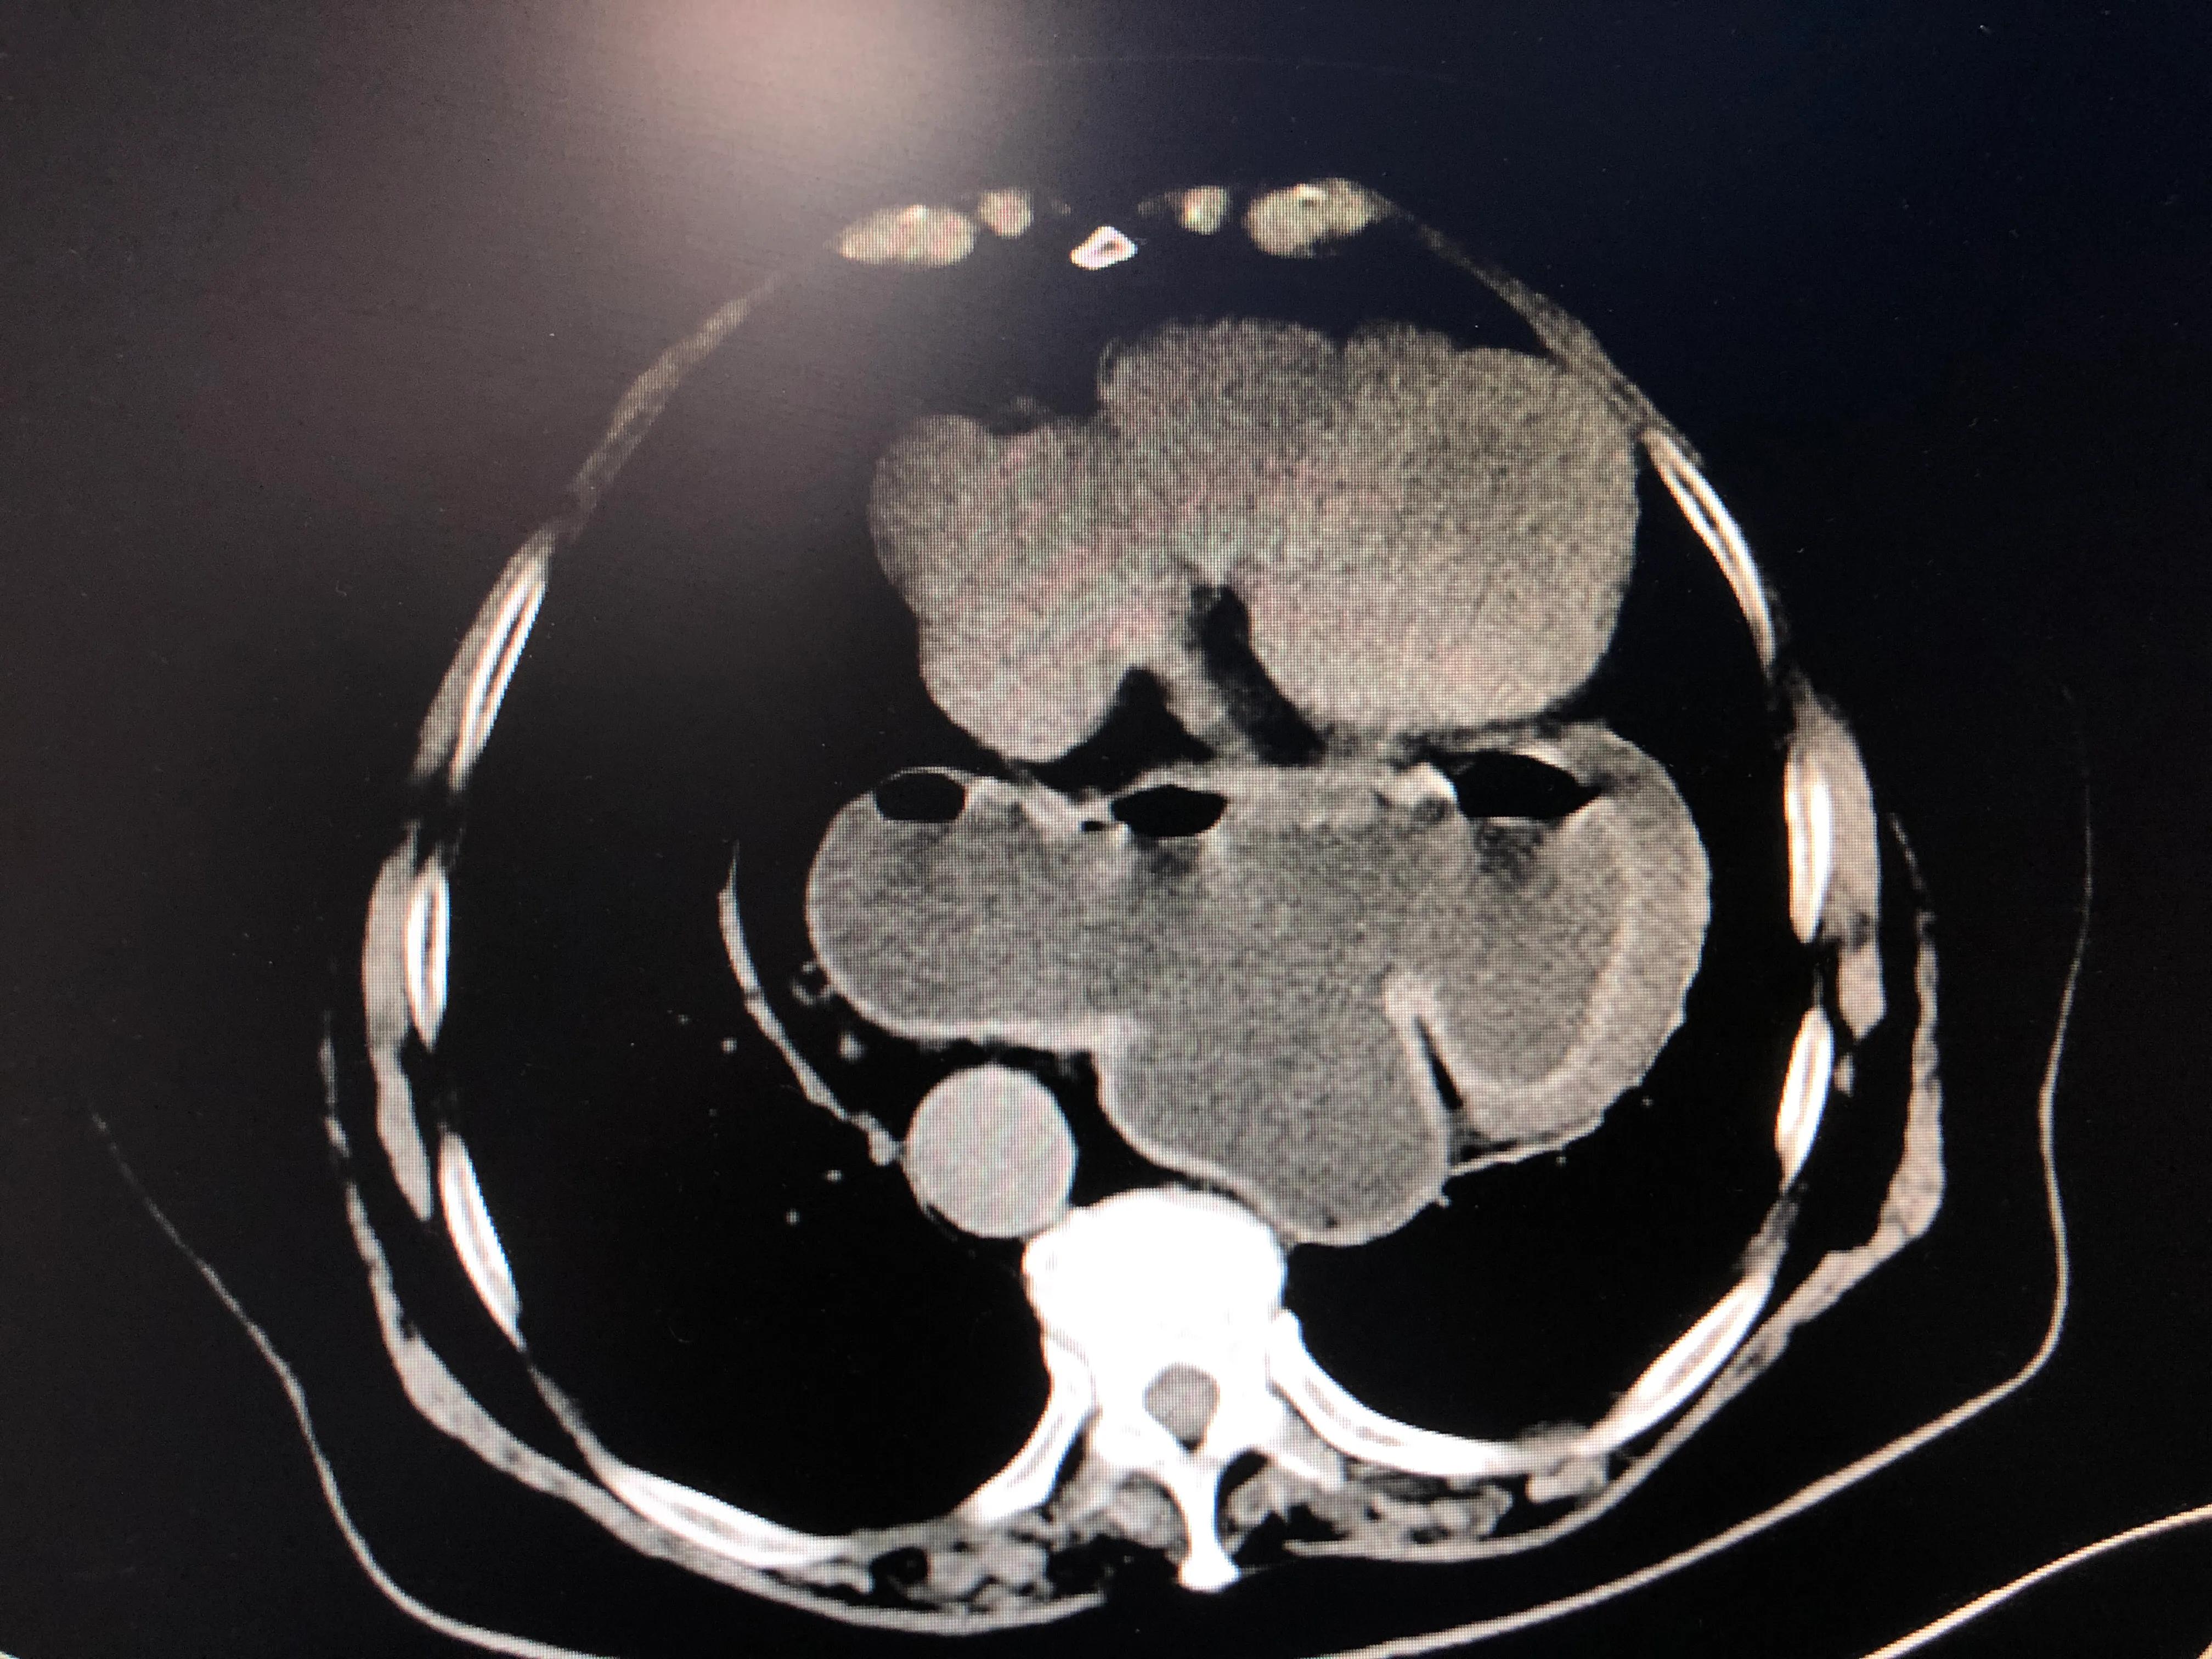

77岁的张女士喘憋不适逐渐加重,CT发现大部分的胃跑到胸腔去,压迫肺脏及心脏,如下图:

该病诊断食管裂孔疝。

巨大食管裂孔疝进入胸腔主要就是占了心脏和肺的地盘( 打个比方: 本来一人一个房间的胸腔,来了一个陌生的胖大胃挤他们的空间,心脏和肺脏被挤压受伤)也就是说,有一部分心肺症状其实是巨大食管裂孔疝引发的,只有做了手术才能缓解( 小提示: 这种情况下不做手术是无解的噢)。

胃肠外科孙作成主任医师为患者制定详细治疗方案,在熟练解剖情况下,完成微创治疗,还原胃的解剖位置,修补食管裂孔巨大缺损,并进行Nissen胃底折叠术(360度经腹胃底折叠术)